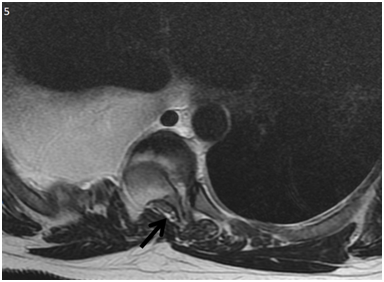

The laboratory studies initially included blood count, serum electrolytes (sodium, potassium, chloride, phosphorus, calcium), coagulation times and liver function tests, where only elevation of leukocytes with predominance of neutrophils was observed, which were associated with the infectious process. The rest of the laboratory tests were within normal ranges. The study of the pleural fluid showed exudate with Gram negative stain, smear microscopy and negative cultures. Therefore, diagnosis of typical parapneumonic effusion was integrated. It was managed with antibiotic therapy and thoracentesis with evolution towards improvement. During hospitalization, progression of bone lysis was observed in the right scapular region and right rib cage, which is why an approach was made to rule out the possible causes of osteolysis.Laboratory studies included: TSH: 1.071mU / L (T3 and T4 were not performed)Glucose 100mg / dLCD3 lymphocyte subpopulations: 472 / 69.2%CD4: 84 / 12.3% CD8: 306 / 44.8% C4 / CD8 ratio: 0.3 C3 complement: 118C4: 29 IgG: 1620 IgM: 125 IgE: 93.9Anticardiolipin IgM 2.3 MPL u / mL IgG GPL u / mL 4.90Antinuclear antibodies: mitochondria anti JO-1, anti-SCL-70, anti-DNAdc, anticelHEP-2 positiveAntinuclear antibodies DNA: ro. anti-ant9 sm / rnp, anti-JO-1, anti SCL-70, anticentromere negative, paratohormone 10 pg / mL The patient was also assessed by the orthopedic service for the congenital scoliosis,  T4-T5 listhesis and T6 compression of medullary canal (Figure 5). It was managed with sublaminar wiring and placement of Luque bars from T2 to T10 and medullary decompression at the T6 level (Figures 6 and 7). The was discharged after the surgical procedure, without supplementary oxygen and in control by external consultation.

<strong>Figure 5 </strong> Magnetic Resonance Imaging, axial acquisition enhanced in T2. Spinal canal stenosis with spinal cord compression (black arrow).

Figure 5 Magnetic Resonance Imaging, axial acquisition enhanced in T2. Spinal canal stenosis with spinal cord compression (black arrow).